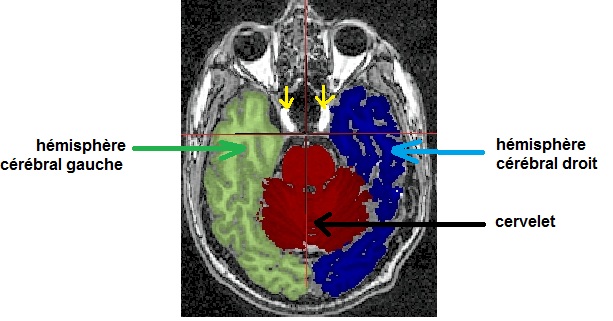

anatencephale